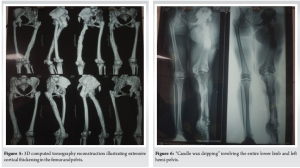

A 28-year-old woman arrived with a 20-year history of gradually increasing pain, swelling, and deformity of the left hemibody, particularly the lower limb, accompanied by functional scoliosis with right-side convexity. Symptoms first appeared in childhood. Upon examination, notable hypertrophy and joint stiffness were observed in the left lower limb (Fig. 1), with a 4.5 cm length discrepancy in the left lower limb, left-sided genu valgum, foot varus, and equinus deformity, along with hyperpigmentation and a scar over the left ankle. The skin over the lumbar region exhibited hyperpigmentation with a 4.5 cm soft tissue swelling at the L3 level (Fig. 2) and nodular thickening over the medial malleolus. Hip and knee fixed flexion deformities measured 25° and 90°, respectively. Digital radiographs and computed tomography (CT) scans demonstrated diffuse cortical thickening and hyperostosis affecting the pelvis, femur, tibia, talus, calcaneus, and tarsal bones of the left side, with partial joint fusion and medullary cavity obliteration, characteristic of “candle wax dripping” [4] (Fig. 3-7).

Melorheostosis, first designated in 1922 by Leri and Joanny [6], remains an exceedingly rare condition that can manifest at any age with equal prevalence among both sexes. Its etiology remains unclear, though hypotheses include defects in mesenchymal cell differentiation (notably mutations in LEMD3)[7], vascular anomalies, and inflammatory processes, though none have been definitively confirmed. In osteoblastic regulation, research by Kim J-E has indicated that adhesion proteins, particularly the transforming growth factor ß-induced gene product, may be downregulated. This occurrence might lead to hyperostosis and associated soft tissue abnormalities [8]. One conceivable explanation is a loss-of-function mutation in the LEMD3 gene (12q12–12q14.3), which is essential for bone morphogenic protein and tumor growth factor-β pathways. These genetic links emphasize the need for further research to clarify causative mechanisms and explore the potential of gene therapy in disease management. Manifestations vary widely, from asymptomatic cases to severe pain and deformity. Symptoms usually develop insidiously, presenting with pain, stiffness, skin changes, and skeletal deformities. Our patient reported pain beginning at age eight, progressing gradually with worsening deformity. Lesion distribution ranges from monomelic (affecting one limb, the most common form) to hemimelic (involving both upper and lower limbs). It may be monostotic (impacting a single bone) or polyostotic (affecting multiple bones). In this case, the disease presented in a hemimelic, polyostotic form, an atypical occurrence. While melorheostosis predominantly affects long bones, axial skeletal involvement is rare. In addition, it has been linked to neoplasms, such as malignant fibrous histiocytoma, osteogenic sarcoma, and dermoid tumors. Differential diagnoses include osteopathic striata, parosteal osteosarcoma, osteopoikilosis, myositis ossificans, and osteoma, particularly in forme fruste cases. In this patient, the diagnosis was straightforward based on clinical presentation, radiographic findings, CT imaging, and histological features. Diagnosis relies primarily on radiographic findings, with classic “dripping candle wax” appearance distinguished by cortical hyperostosis, increased bone thickness, linear density extending into cancellous bone [9]. In this case, radiographic evidence clearly supported the diagnosis. Laboratory investigations were unremarkable, a hallmark of this condition. Histopathological findings generally lack specificity, with a heterogeneous mix of mature and immature bone forming a dense structure with elevated trabecular bone. While osteoclastic activity has been uncommon, mild osteoblastic proliferation is frequently observed, aligning with findings in this case. Treatment is predominantly symptomatic, with most patients undergoing non-operative management. Surgery is reserved for cases involving contractures and severe deformities, including tendon lengthening, osteotomies, excision of hyperostotic bone, or, in extreme cases, amputation [10]. Our patient was prescribed aceclofenac 100 mg twice daily, which provided symptom relief. Melorheostosis remains an exceedingly rare disorder marked by linear hyperostosis laterally the cortical bone. On the clinical level, it manifests localized pain and deformity, and the diagnosis is determined through combining of imaging and clinical assessment. No definitive treatment exists, as well as management focuses primarily on symptomatic relief.